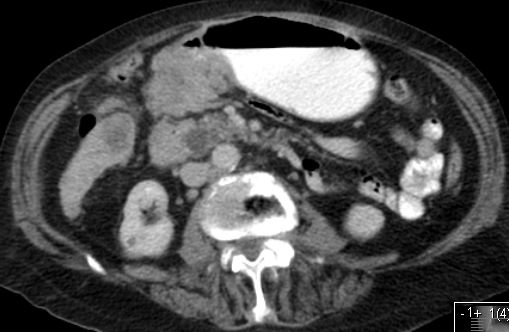

| CT | Obstruierendes Magenantrumkarzinom. Ausgedehnte Lebermetastasen. | 66jährige Frau nach Gastektomie: Lebermetastasen.![]() | |

| CT | Magenkarzinom an der großen Kurvatur mit Lymphknotenmetastasen. Ausgedehnte Lebermetastasen.![]() |